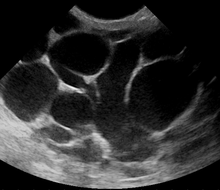

However, if the doctor is not sure whether the mass is an abscess or a tumor, a breast ultrasound may be performed. The ultrasound provides a clear image of the breast tissue and may be helpful in distinguishing between simple mastitis and abscess or in diagnosing an abscess deep in the breast. The test consists of placing an ultrasound probe over the breast.

Breast abscess

An abscess (or suspected abscess) in the breast may be treated by ultrasound-guided fine-needle aspiration (percutaneous aspiration) or by surgical incision and drainage; each of these approaches is performed under antibiotic coverage. In case of puerperal breast abscess, breastfeeding from the affected breast should be continued where possible.[2][29]

For small breast abscesses, ultrasound-guided fine needle aspiration such as to completely drain the abscess is widely recognized as a preferred initial management.[30]

A recent review article suggested the following line of treatment for suspected breast abscess: initially, antibiotics treatment, ultrasound evaluation and, if fluid is present, ultrasound-guided fine needle aspiration of the abscess with an 18 gauge needle, under saline lavage until clear.[31] The exudate is then sent for microbiological analysis for identification of the pathogen and determination of its antibiotic sensitivity profile (antibiogram),[32] which may in turn give an indication for changing the antibiotics prescription. At follow-up, a mammography is performed if the condition has resolved; otherwise the ultrasound-guided fine-needle aspiration with lavage and microbiological analysis is repeated.[33] If three to five aspirations still do not resolve the condition, percutaneous drainage in combination with placement of an indwelling catheter is indicated, and only if several attempts at ultrasound-guided drainage fail, surgical resection of the inflamed lactiferous ducts (preferably performed after the acute episode is over) should be considered.[34] It is noted, however, that even the excision of the affected ducts does not necessarily prevent recurrence.[34]